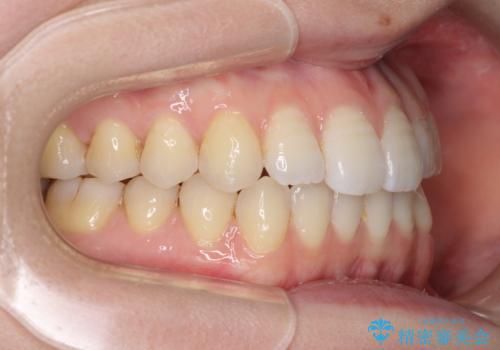

オープンバイトのインビザラインを用いた再矯正

- 矯正治療の後戻りを気にして来院された患者様です。

オープンバイト(前歯の開咬)と下顎骨の偏位による不正咬合が認められました。

骨格の偏位による不正咬合は改善しきれないことを理解いただいた上で、インビザラインにて矯正治療を行うこととしました。

オープンバイトは後戻りを起こしやすいため、極力そのリスクを軽減するため、奥歯を圧下させるように治療を進めていきました。

下顎骨の偏位が顕著であったため、上下の正中を合わせることはできませんでしたが、患者様には大変満足していただきました。